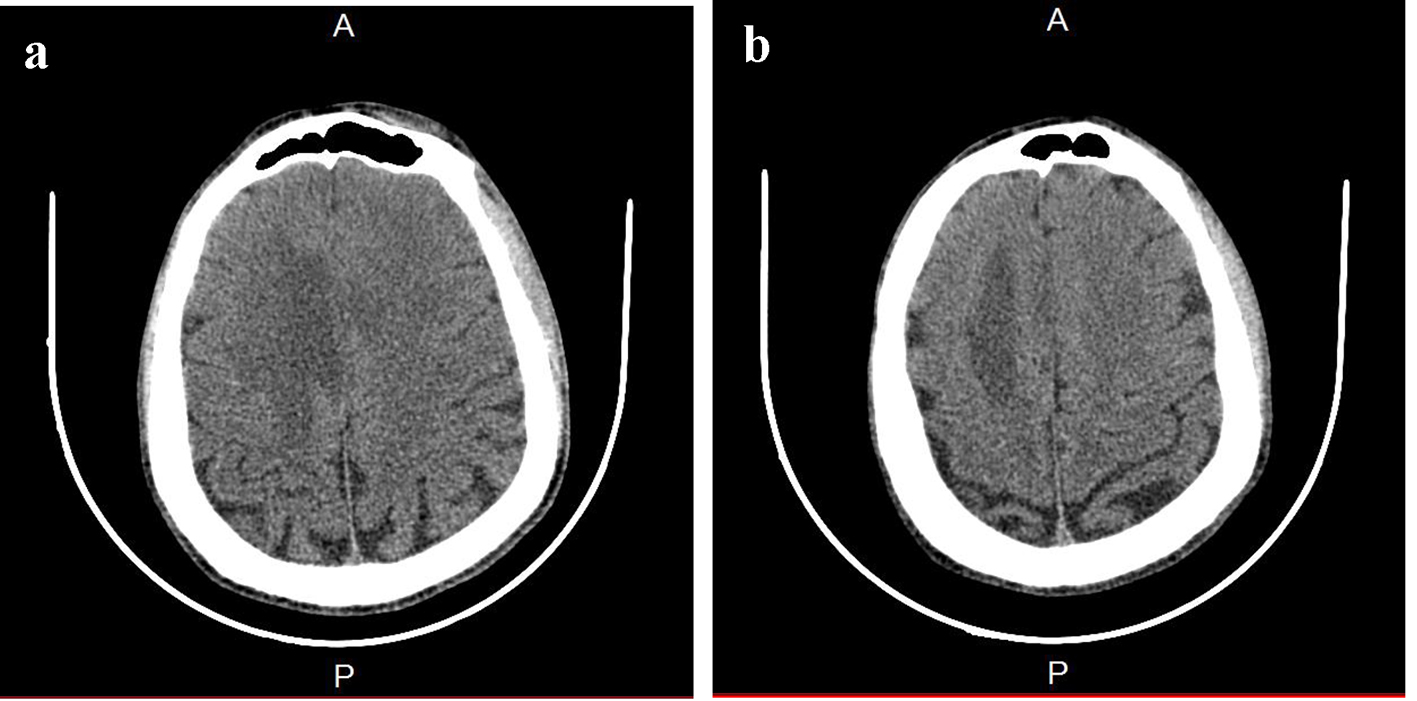

Figure 1. Brain CT. (a) A paramedian right low density area located in the corpus callosum and in the white matter of the right centrum semiovale. (b) A hypodense zone with a discrete mass effect on the right ventricle.